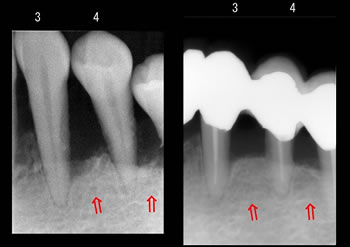

かなり重度の歯周病でグラグラでしたが、仮歯のブリッジで連結固定しまして、歯周外科療法によりエムドゲイン歯周組織再生療法を行いました。

お口の中の同じ部位で「左が初診時」で「右が再生治療後」のレントゲンです! |

赤い矢印の部分が歯槽骨の再生した場所です。

(3は3番目の歯、4は4番目の歯です) |

再生された骨の縁に白いライン(歯槽硬線)がありますよね!

重要!

左の方は骨の縁がモヤモヤっと虫に喰われてみたいにぼんやりしてますが、右の治療後は再生されたうえに歯槽硬線がハッキリ見え、かなり安定しています! |